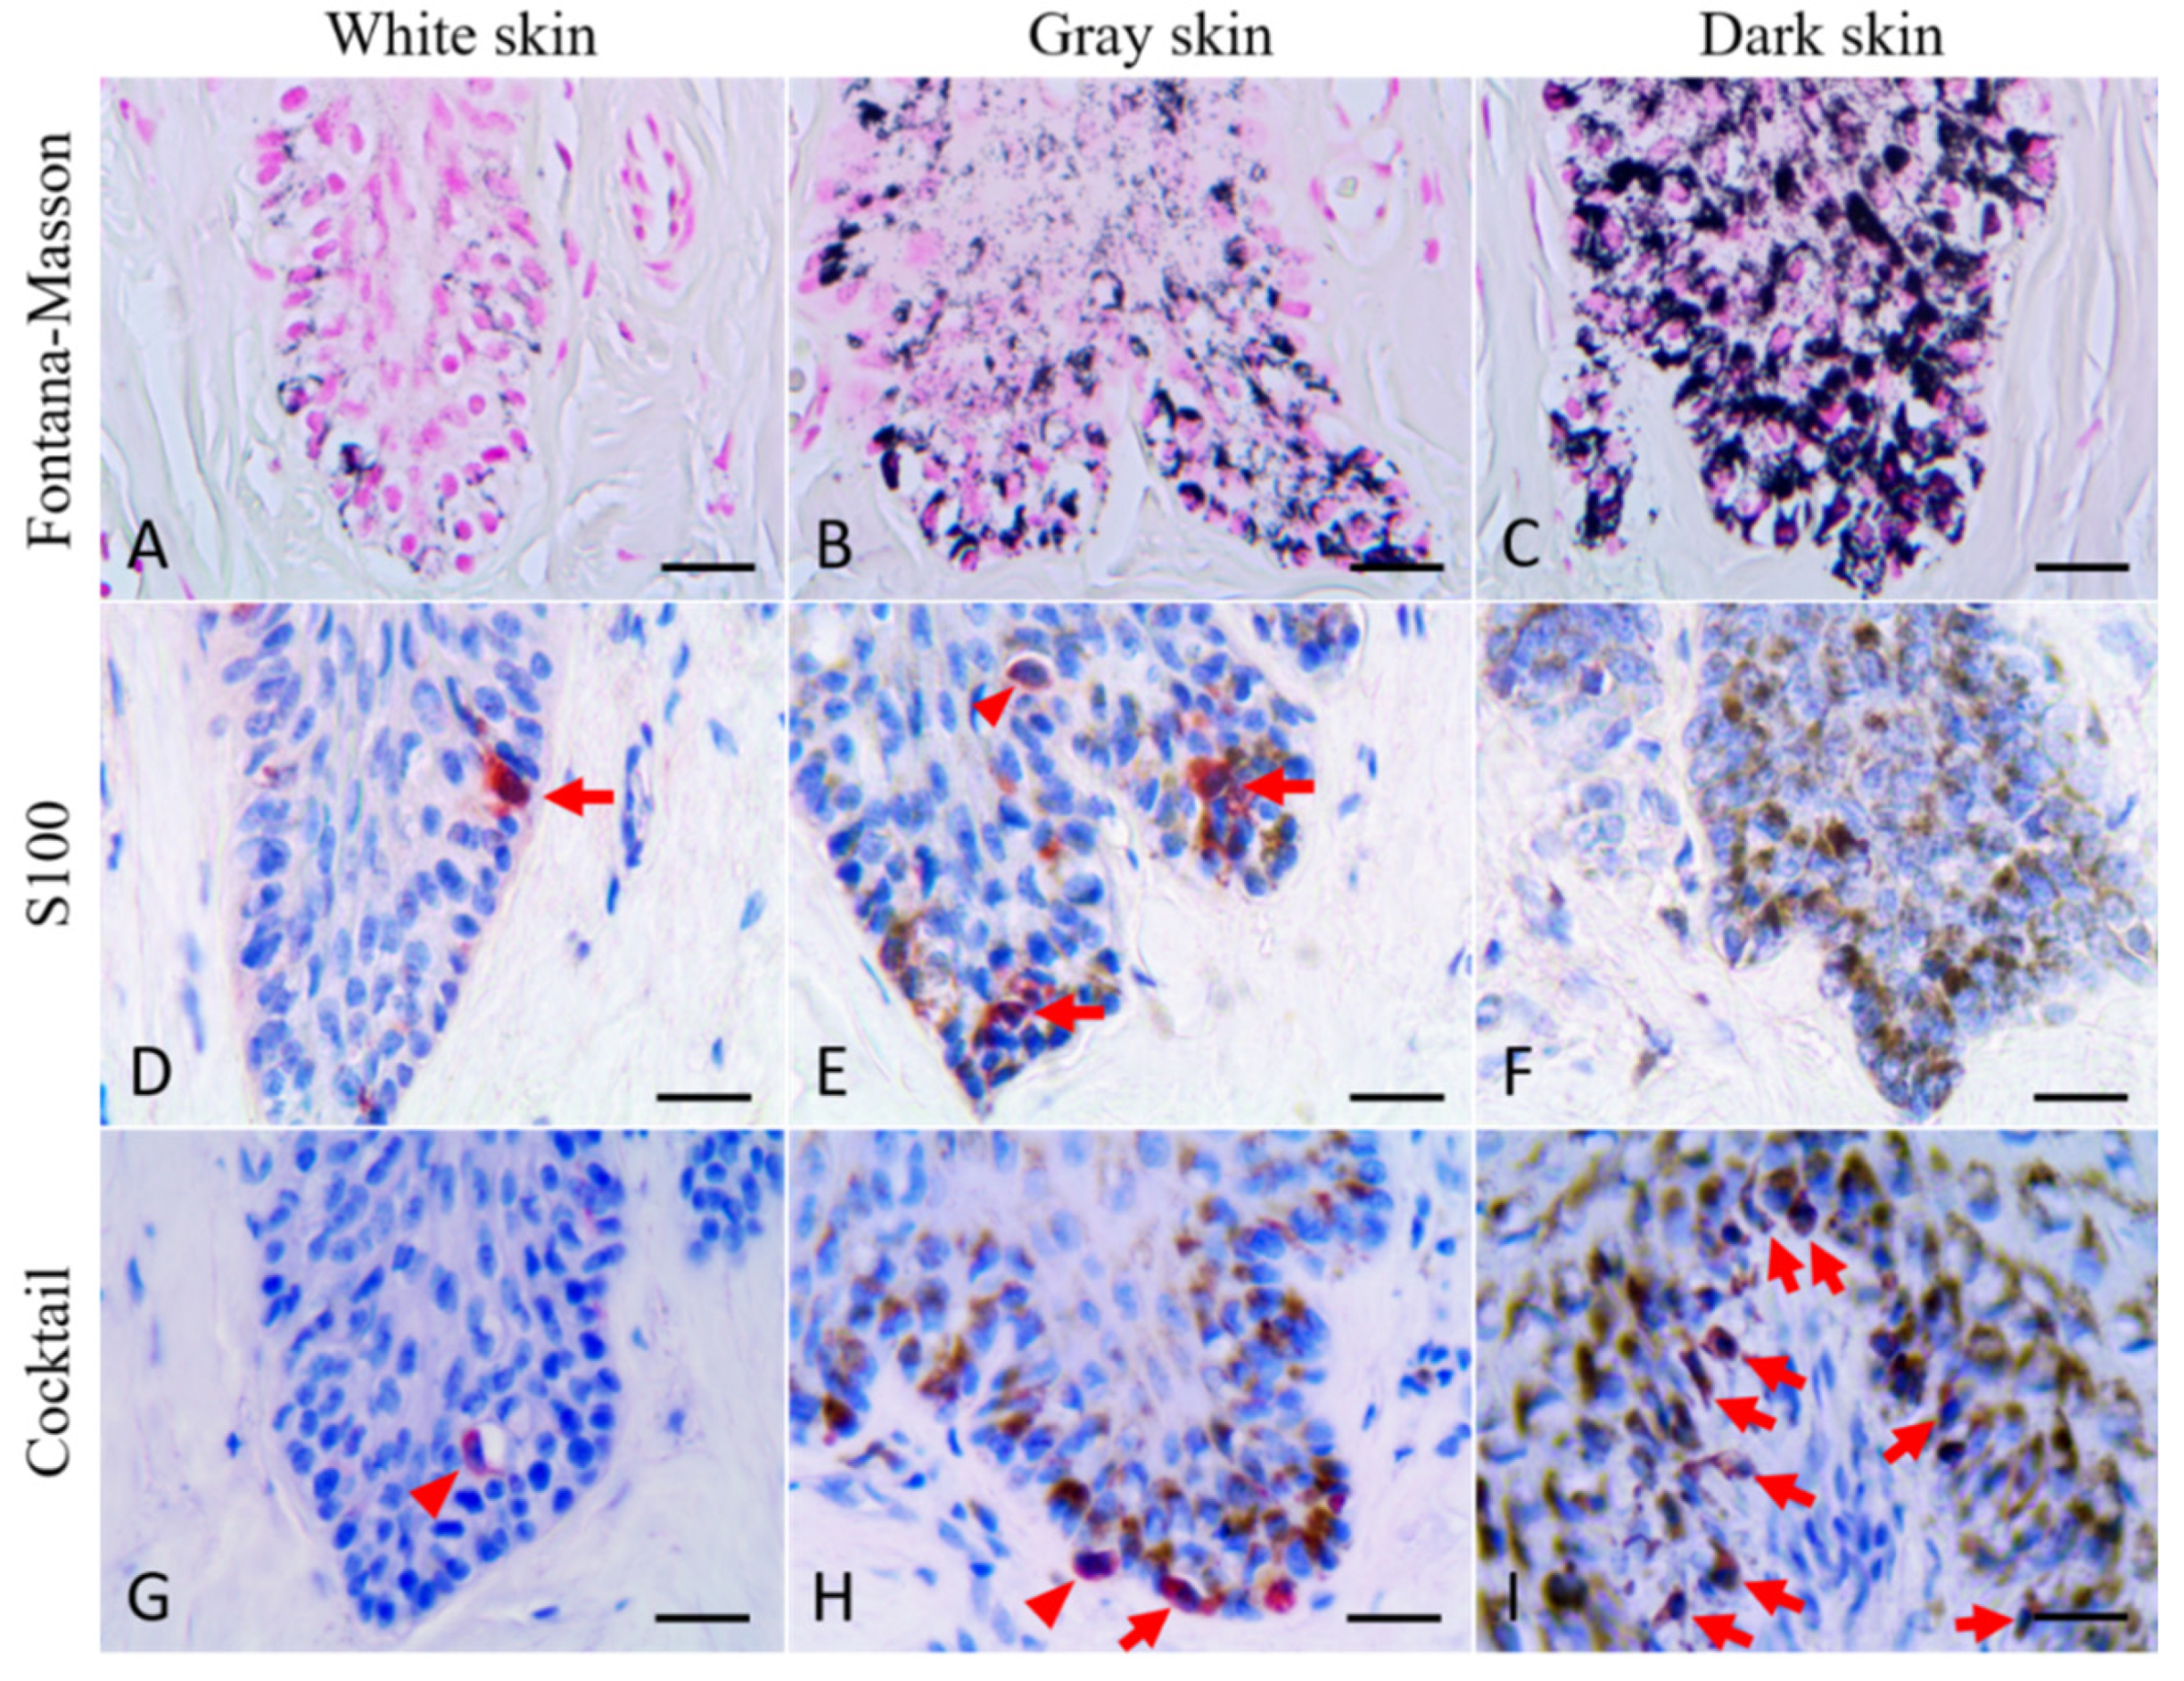

3.1. Fontana–Masson Staining

3.2. Immunofluorescence Staining

3.3. Immunohistochemical Staining